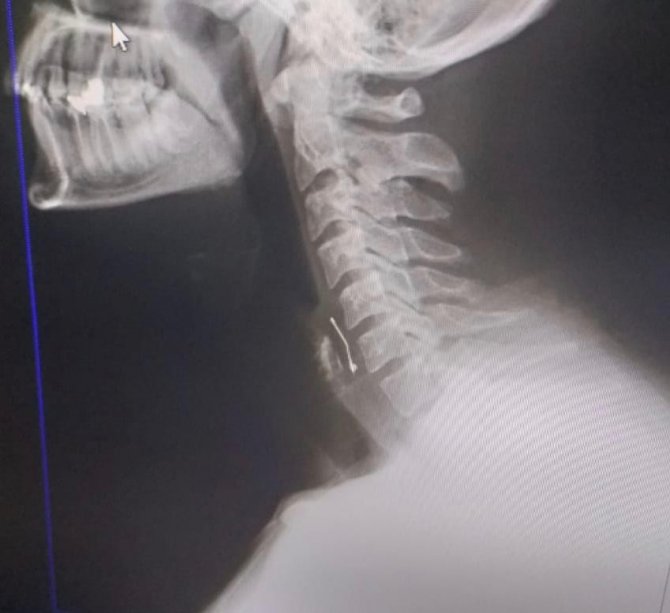

Edinilen bilgiye göre, arkadaşının doğum gününü kutlamak için Tekerek mevkisinde bir pastaneye giden Ramazan Orçan (22),pastayı yedikten sonra fenalaşınca Kahramanmaraş Sütçü İmam Üniversitesi (KSÜ) Tıp Fakültesine götürüldü. Yapılan kontrollerde boğazına toplu iğne saplandığı tespit edilen genç, acil ameliyata alındı. Ameliyatla boğazına saplanan iğne çıkarılan Ramazan Orçan'ın tedavisi sürüyor.

Ramazan Orçan, "Perşembe akşamı arkadaşlarımla birlikte Tekerek'te bulunan bir pastaneye doğum günü kutlamak için gittik. Biraz oturduktan sonra yaş pasta masamıza geldi. Ben pastadan birkaç defa aldım. Boğazıma bir şeyin battığını ve nefes alamadığımı hissettim. Acil olarak pastaneden ayrıldık ve Kahramanmaraş Sütçü İmam Üniversite Acil Servisine geldik. Burada yapılan tetkikler sonucu boğazımda bir toplu iğne olduğu kanısına varıldı. Defalarca operasyon geçirdim. Yoğun uğraşlar sonucunda toplu iğne boğazımdan çıkarıldı. Şuan hastanede yatıyorum. Bir süre daha gözetim altında tutulacağım. Ölümle kalım arasında kaldığımı doktorlar ifade etti. Benim başıma geldi, başkalarının başına gelmesin. Olayı yargıya taşıyacağım" dedi.